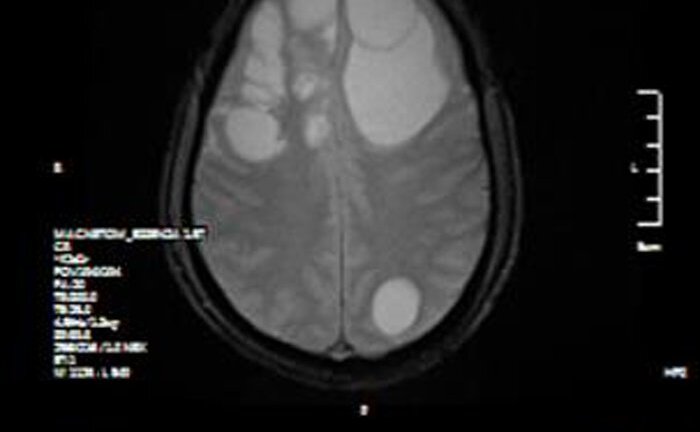

Ổ sán khổng lồ 'lúc nhúc' trong não người đàn ông ở Phú Thọ

Ổ sán khổng lồ cư trú trong não khiến người đàn ông ở Phú Thọ mất dần trí nhớ, phù não diện rộng, phải phẫu thuật khẩn cấp.